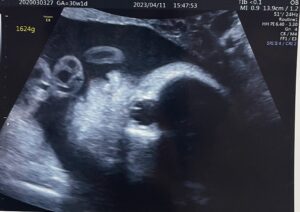

経腹エコー(4D)

そして経腹エコーの結果、冒頭で書いた通り、また逆子ちゃんに。

でも不思議だったのは、2週間前に比べて130gほどしか体重が増えていなかったこと。

先生も「まだそんなに大きくなっていないし、羊水量もしっかりあるから回ると思うよ」とおっしゃっていました。回ってくれるといいなぁ。

4Dのエコーの最中にお腹の中で赤ちゃんがすごく動いていて、映像が乱れていたのが怖かったです^^;